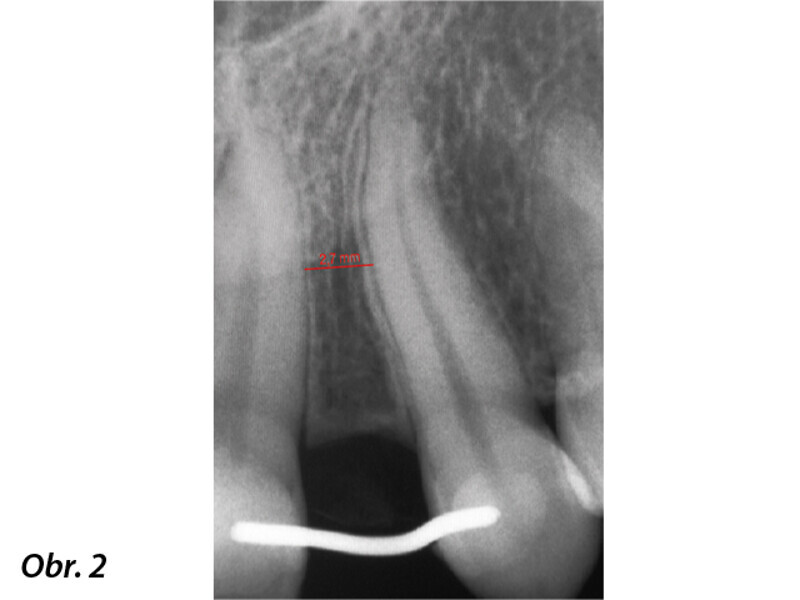

Aproximální rozšíření mezi kořeny zubů za účelem zavedení úzkého implantátu